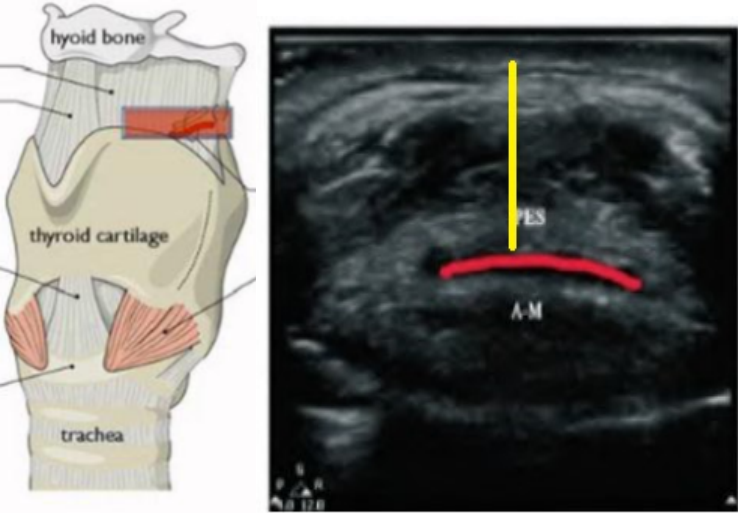

图17为肺超(低频凸阵探头),经腋中线做垂直肋骨的M型超声下可见“肺搏动征”。

图片

图17  肺超低频凸阵探头

图18为膈肌超声,锁骨中线与肋缘的交界处(凸阵低频探头),探头标志朝向外侧,M超模式下观察膈肌运动幅度。

图18  膈肌超声,锁骨中线与肋缘的交界处(凸阵低频探头)